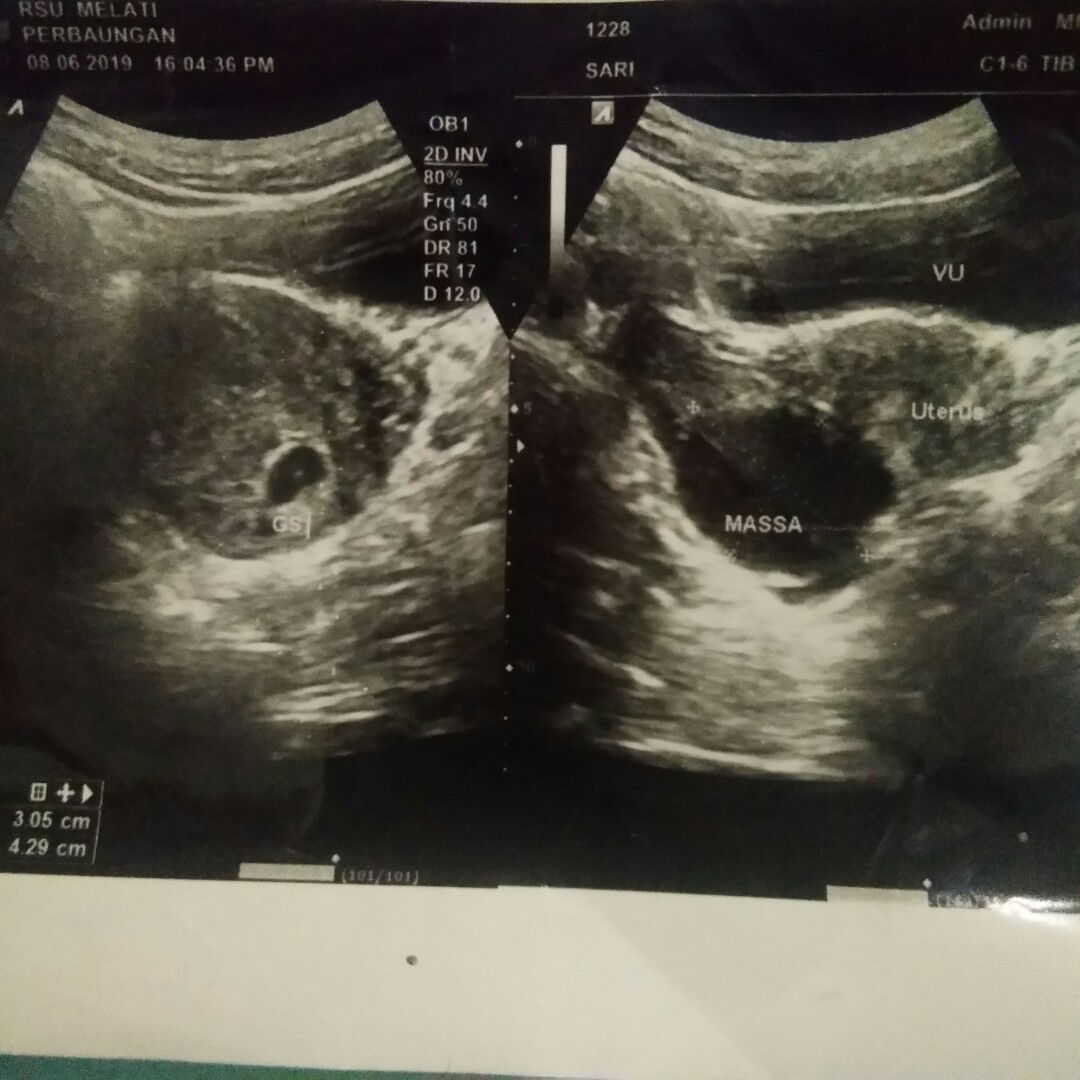

Ada kista

Saya bulan lalu telat haid 2minggu tespek positif langsung ke RS Usg bun.. Ternyata kistanya jg saya langsung kaget pdahal saya haid lancar selalu, ga ada keluhan sakit atau apapun paling biasa nyeri pas dtg bulan kayak pada umumnya.. Dan diUsg keliatan kantung janinnya, itu ada titik ditengah kntung mudah2an itu bakal janinnya ?? Nah bulan ini saya mau Usg lagi.. Mudah2an janinnya berkembang dengan baik ? dan kistanya mengecil ??